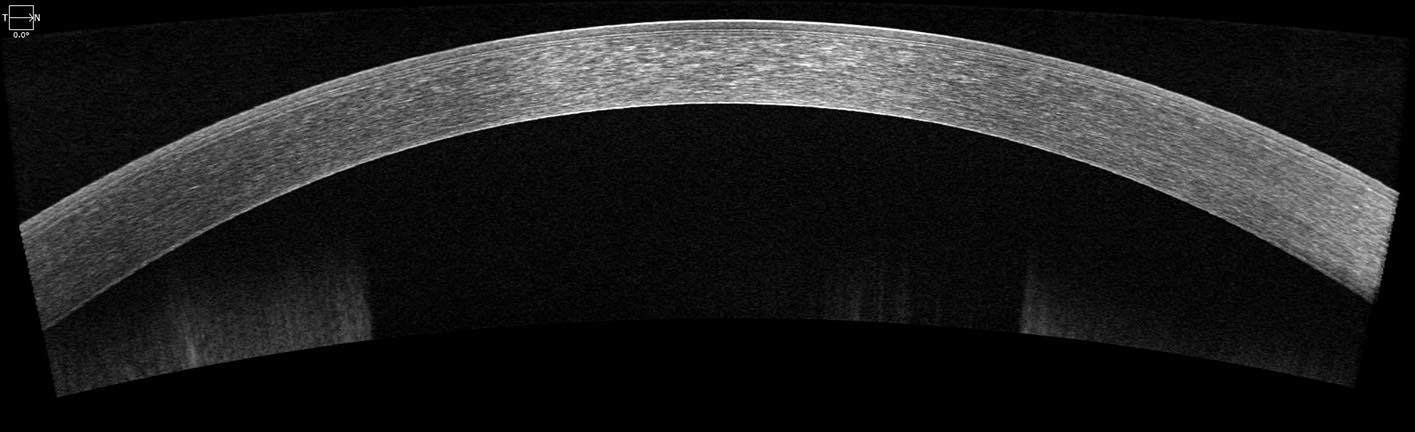

Another useful application is the use of OCT to scan the cornea, this is the clear structure at the front of the eye. There are five layers in the cornea: epithelium, bowman’s layer, stroma, descents membrane and endothelium. These scans are particularly useful in patients who have had corneal transplant surgery, the surgeon can assess outcome of the surgery by viewing the endothelium, checking for detachments.